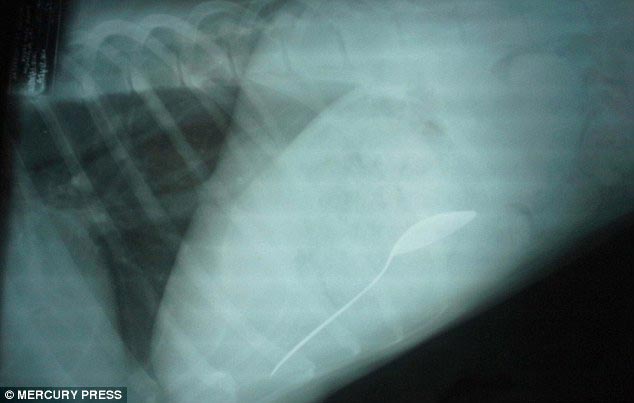

Врачи были очень удивлены, обнаружив большой кусок неизвестной массы в животе 40-килограммового боксера

![Что на ужин? Рентгеновские снимки животных, с шокирующими предметами извлеченными из их желудков предметы извлеченные из желудков животных, рентгеновские снимки животных съевших предметы, необычные предметы съели животные]()

Как выяснилось, этой массой был огромный кусок клея, который по всей видимости собака стала есть в жидком состоянии, и который в последствии застыл у неё в животе